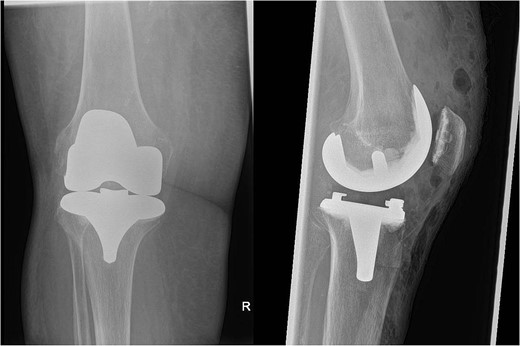

Over the following month, the skin above the fractured patella became necrotic, resulting in an open discharging wound. It was now clear that infection was the issue. With Orthoplastics involvement, she underwent multiple tissue samplings, patellectomy, removal of implants, and insertion of an antibiotic impregnated cement spacer (Fig. 3). Over the ensuing days the infection was uncontrollable despite further debridement and appropriate multi-drug antibiotic therapy. Following a multi-disciplinary team decision, a staged Above Knee Amputation (AKA) was performed (Fig. 3) with negative pressure dressings applied in the interim. Patient was discharged 4 weeks later on achieving closure of the stump. Mobility at discharge was limited to hoist transfers. Unfortunately, the patient passed away 8 weeks later.

On the left X-ray of the knee after removal of prosthesis and insertion of antibiotic-impregnated cement spacer and on the right X-ray of the stump following amputation.